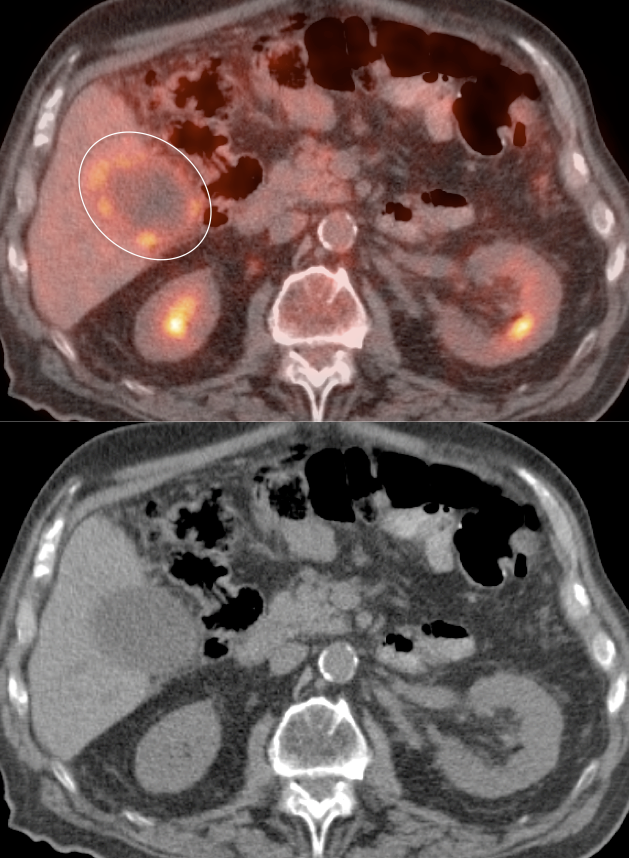

Recurrence & Restaging:

- Restaging suspected recurrence.

- Distinguishing recurrence from post-therapeutic inflammation.